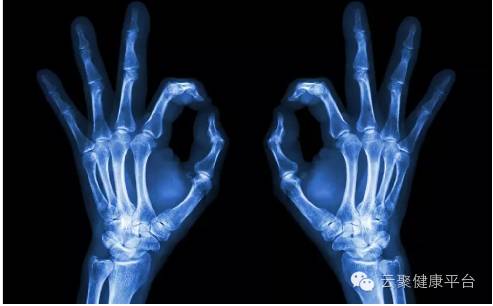

第三剑  X光

X光像把面包压扁了看,X光会穿过人体,遇到被遮挡的部位,底片上不会曝光,洗片后这个部位就是白色的。就像一片面包或一块棉花,看不到里面的纤维纹理,但用手压瘪了会清晰一些。X光最大缺点是受制于深浅组织的影像相互重叠和隐藏,有时需要多次多角度拍摄X光片。

1、外伤骨头——粗看X光片、细看CT

各种外伤,如果怀疑伤到了骨头,优先选择X光照片,检查结果快速易得。若要进一步观察,可以选择CT。超声、核磁对于骨皮质等看不大清,一般不选择。